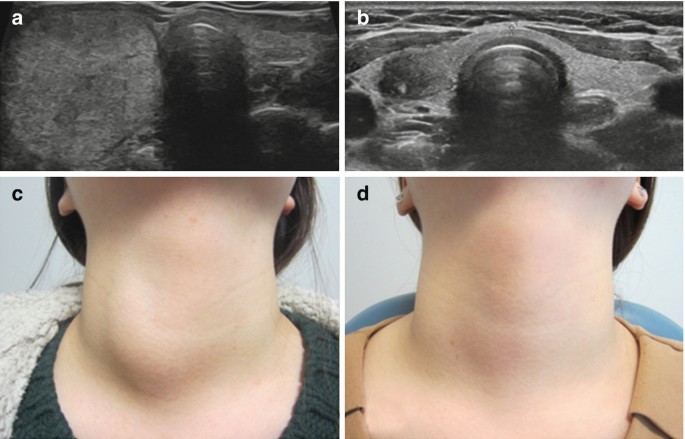

Thyroid Ultrasound

Thyroid Ultrasound

Thyroid Nodule With Taller Than Wide Dimensions Download Scientific